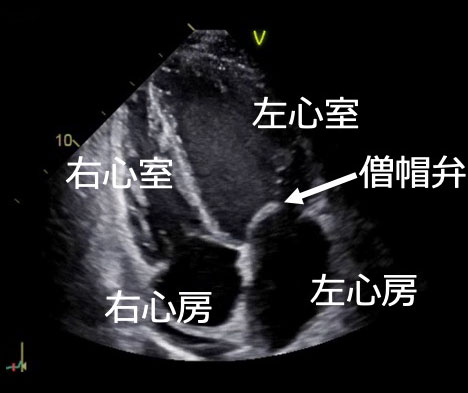

正常な心臓のエコー画像

弁膜症(僧帽弁逆流)のエコー画像

心臓の構造と役割

心臓には図のように4つの部屋があり、それぞれ“弁”で隔てられています。

ポンプの動きに応じて弁が開閉し⾎液の逆流を防いでいます。

心臓は、全⾝に⾎液を送り出すポンプの役⽬をしています。